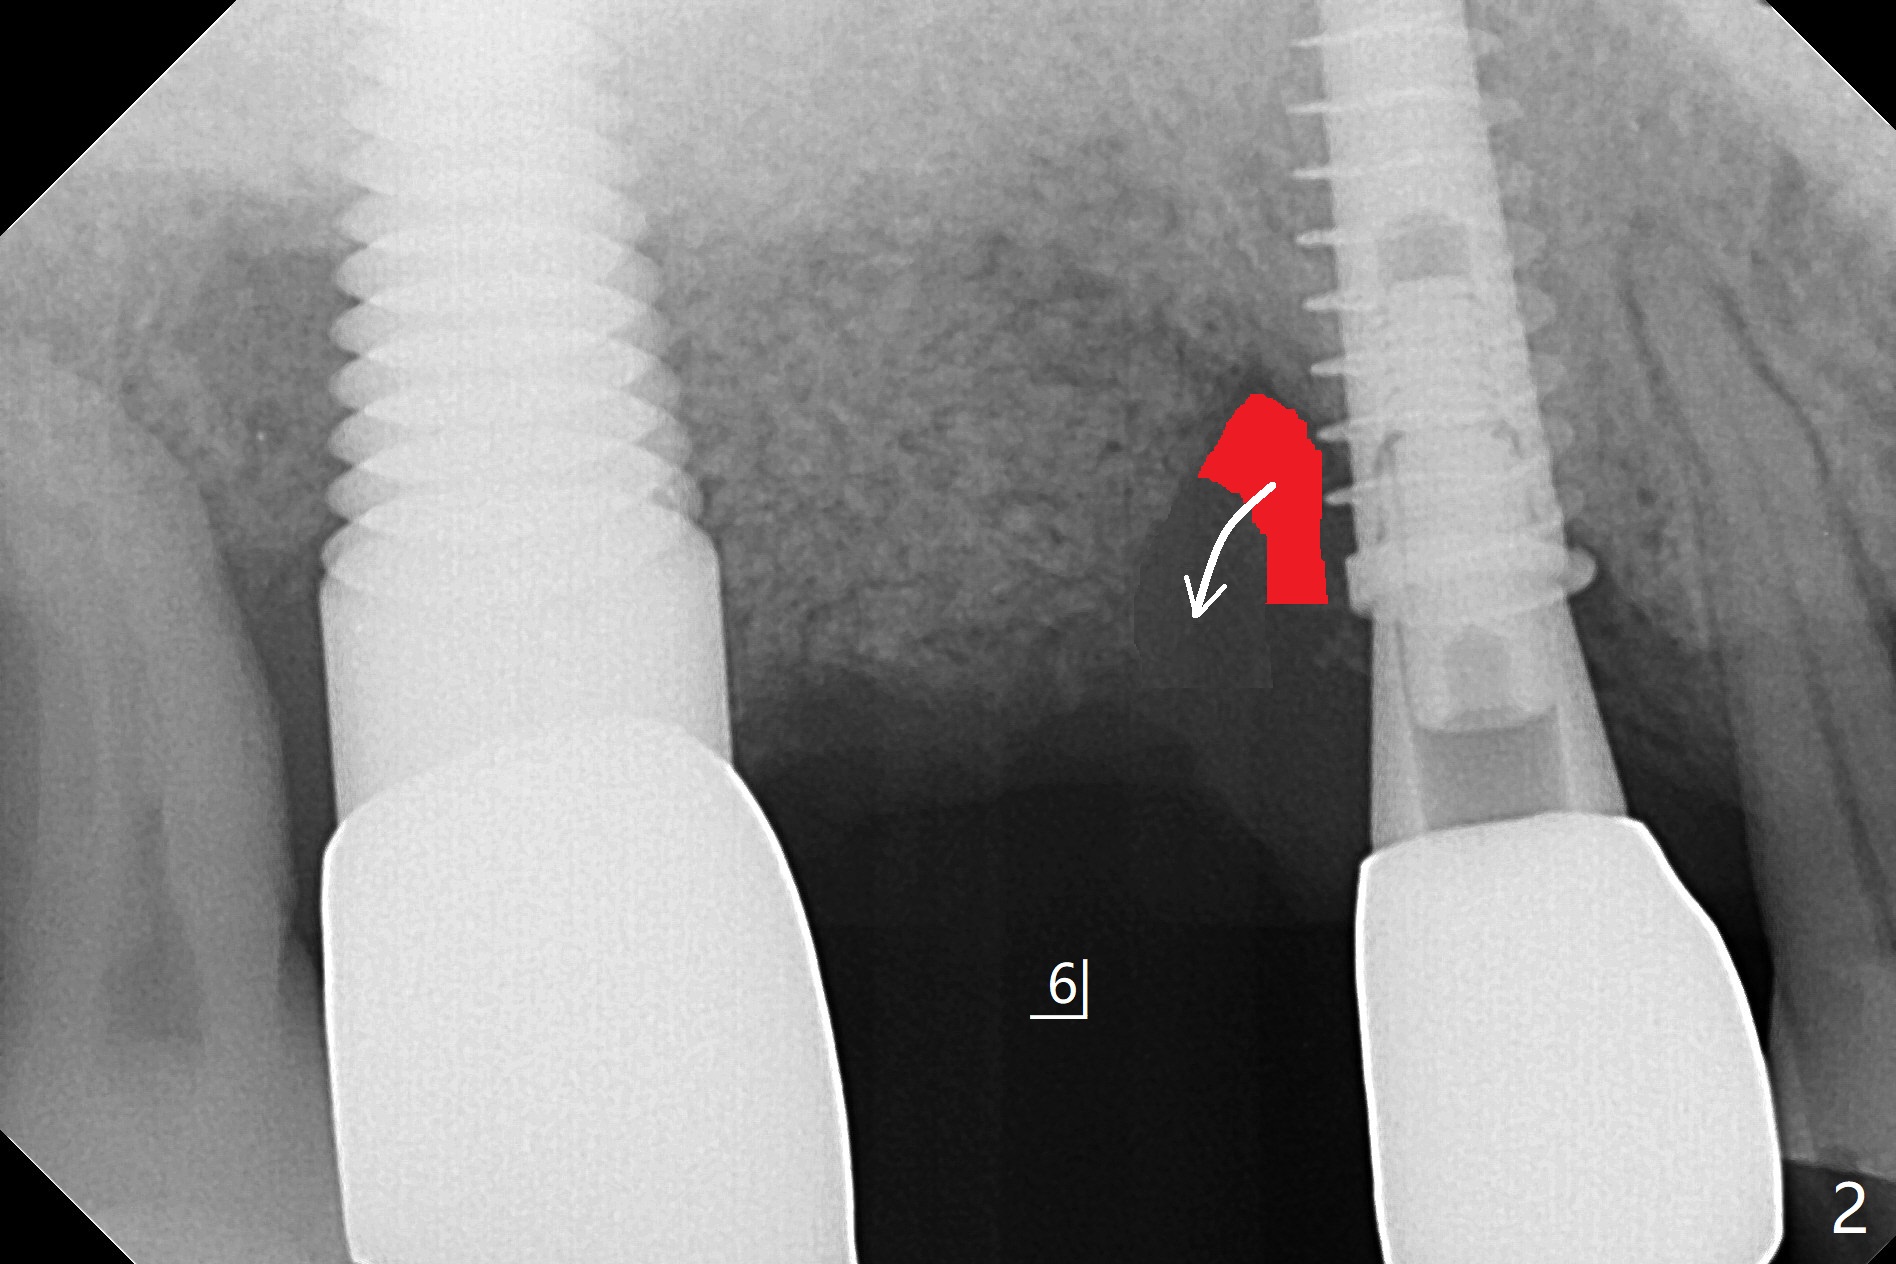

51岁男(牙周炎,咀嚼力大),右上6植体(7x17毫米,即刻种植,当时牙槽窝大,使用大植体,减少骨粉量)使用6年10月后松动,在诊所用手指取出,颊侧牙龈低,刮拔肉芽组织时发现颊侧,腭侧骨壁都缺失,但是没有通入上颌窦,植入粘性骨粉(Vanilla),覆盖一张PRF膜,4-0PGA缝线尽量严密缝合(图一,让口子骨粉有充分血供,相应减少角化龈和骨质高度),然后使用树脂敷料固定(PRF膜很快吸收)。7植体近中螺纹暴露,钛刷清洗后,骨粉放置于表面,而5远中深部螺纹好像暴露,浅部却被牙龈(乳头处)覆盖,所以骨粉无法进入缺失地方(图一:*)。理想的话,应该将牙龈分离(图二:弯箭头),这样骨粉就能进入缺损区域。6愈合后植牙时,用类似方法植骨。术后一周局部卫生好,没有任何不适(图三)。当术后五周树脂敷料取出时,骨粉好像生长不好(图四)。术后两个月伤口愈合(图五),但是骨粉失去不少(图六)。Return to No Caries Xin Wei, DDS, PhD, MS 1st edition 02/09/2021, last revision 08/09/2021